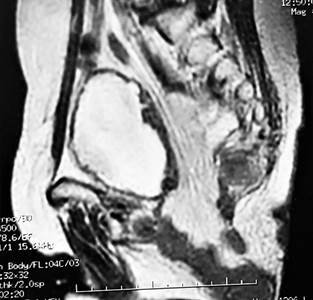

Figura 5. Caso 2: Tomografía computada. Corte sagital que muestra la hernia perineal.

Mujer de 58 años, sin antecedentes de relevancia, sometida a una operación de Miles asistida por videolaparoscopia con cierre primario del periné por adenocarcinoma del recto inferior, consultó al 4º mes postoperatorio con bulto perineal de crecimiento progresivo, disuria y molestia local. Se diagnosticó HP reductible e incoercible (Figs. 4 y 5) Se reparó por abordaje abdominal videolaparoscópico. Luego de liberar escasas adherencias laxas se redujo el contenido hacia la cavidad abdominal procediendo a la reparación del piso pelviano con prótesis de doble revestimiento, fijada a los reparos óseos y músculos del piso pelviano con dispositivo de fijación, sin omentoplastia (Fig. 6). Con buena evolución postoperatoria se otorgó alta institucional al 2º día postoperatorio. A los 12 meses de la cirugía continúa sin recidiva de la hernia (Fig. 7).